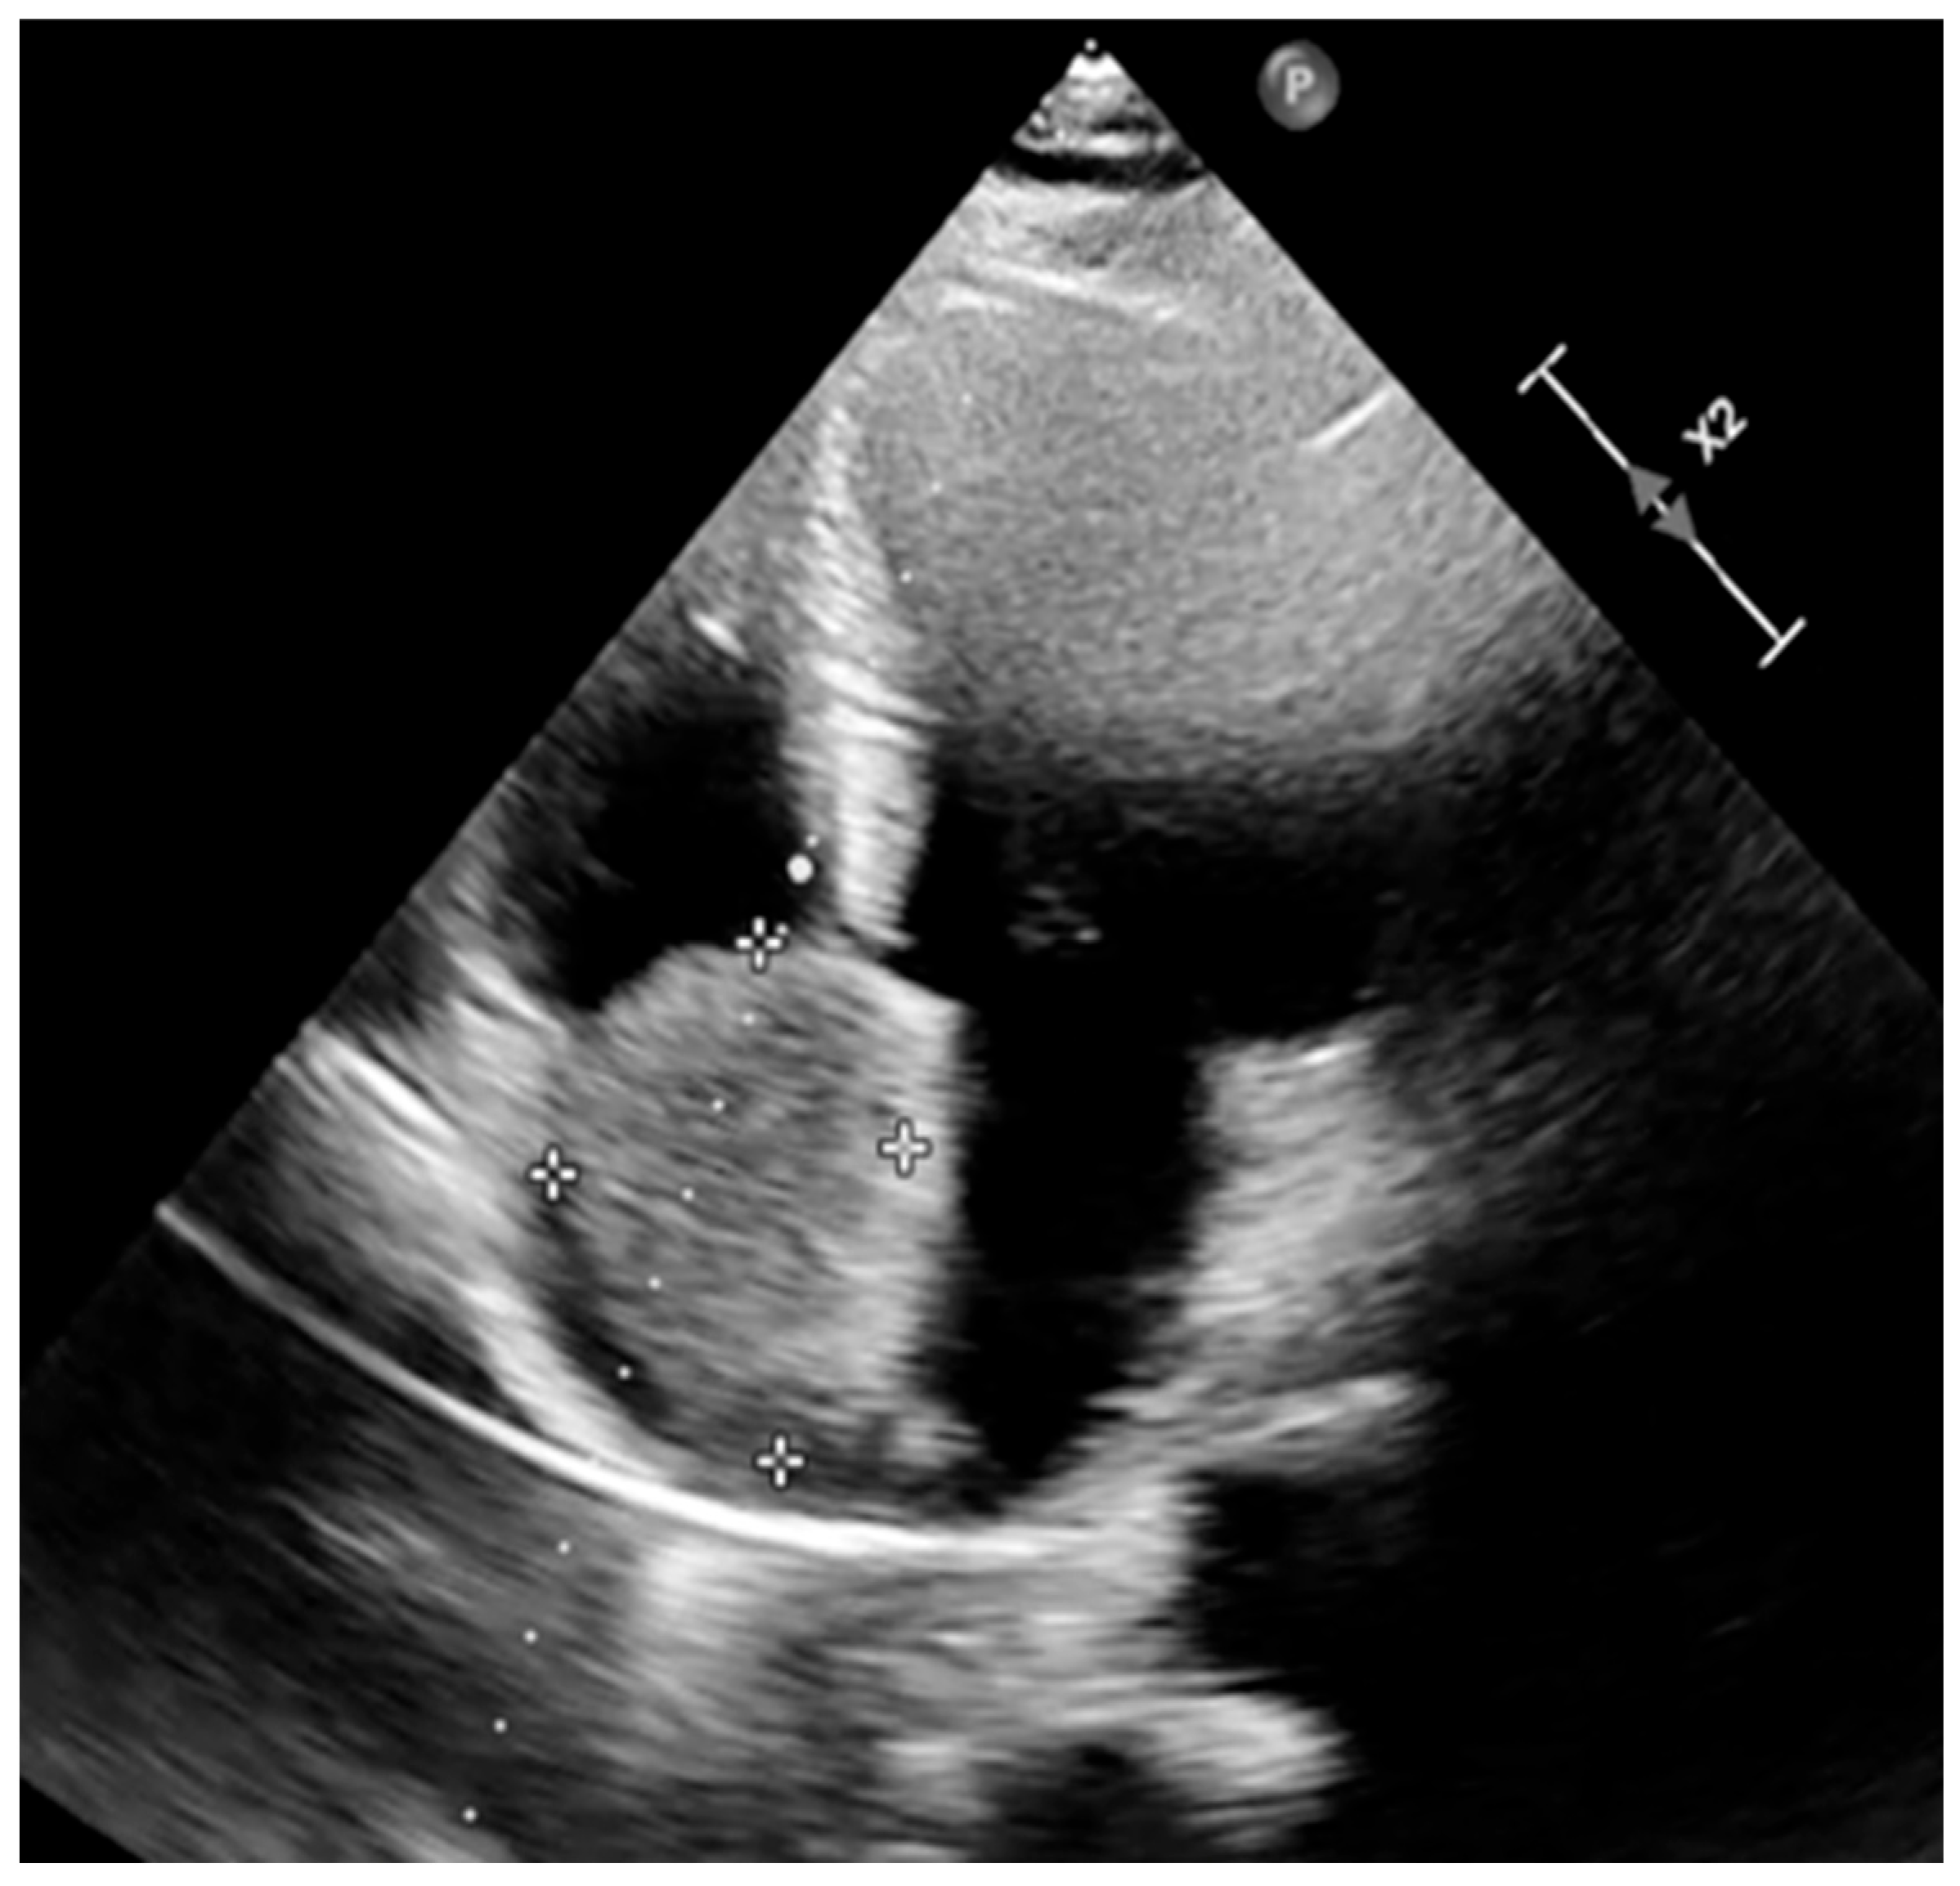

| Day 1 (hospital stay) | Transthoracic echocardiography: 5.5 × 3.5 cm right atrial mass attached at the fossa ovalis; functional tricuspid stenosis with moderate regurgitation; mild degenerative mitral regurgitation; no pericardial effusion. |